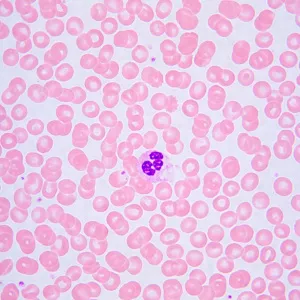

Студенческий микроскоп MAGUS Bio 240B предназначен для профессиональной подготовки. С его помощью можно проводить исследования в проходящем свете по методу светлого поля и изучать прозрачные и полупрозрачные биологические препараты. Микроскоп оснащен кодированным револьвером под 4 объектива с интеллектуальным освещением: его яркость подстраивается под каждый объектив. Прибор имеет небольшие габариты, его удобно перемещать и хранить.

- Микроскоп для исследований в проходящем свете и изучения прозрачных и полупрозрачных препаратов